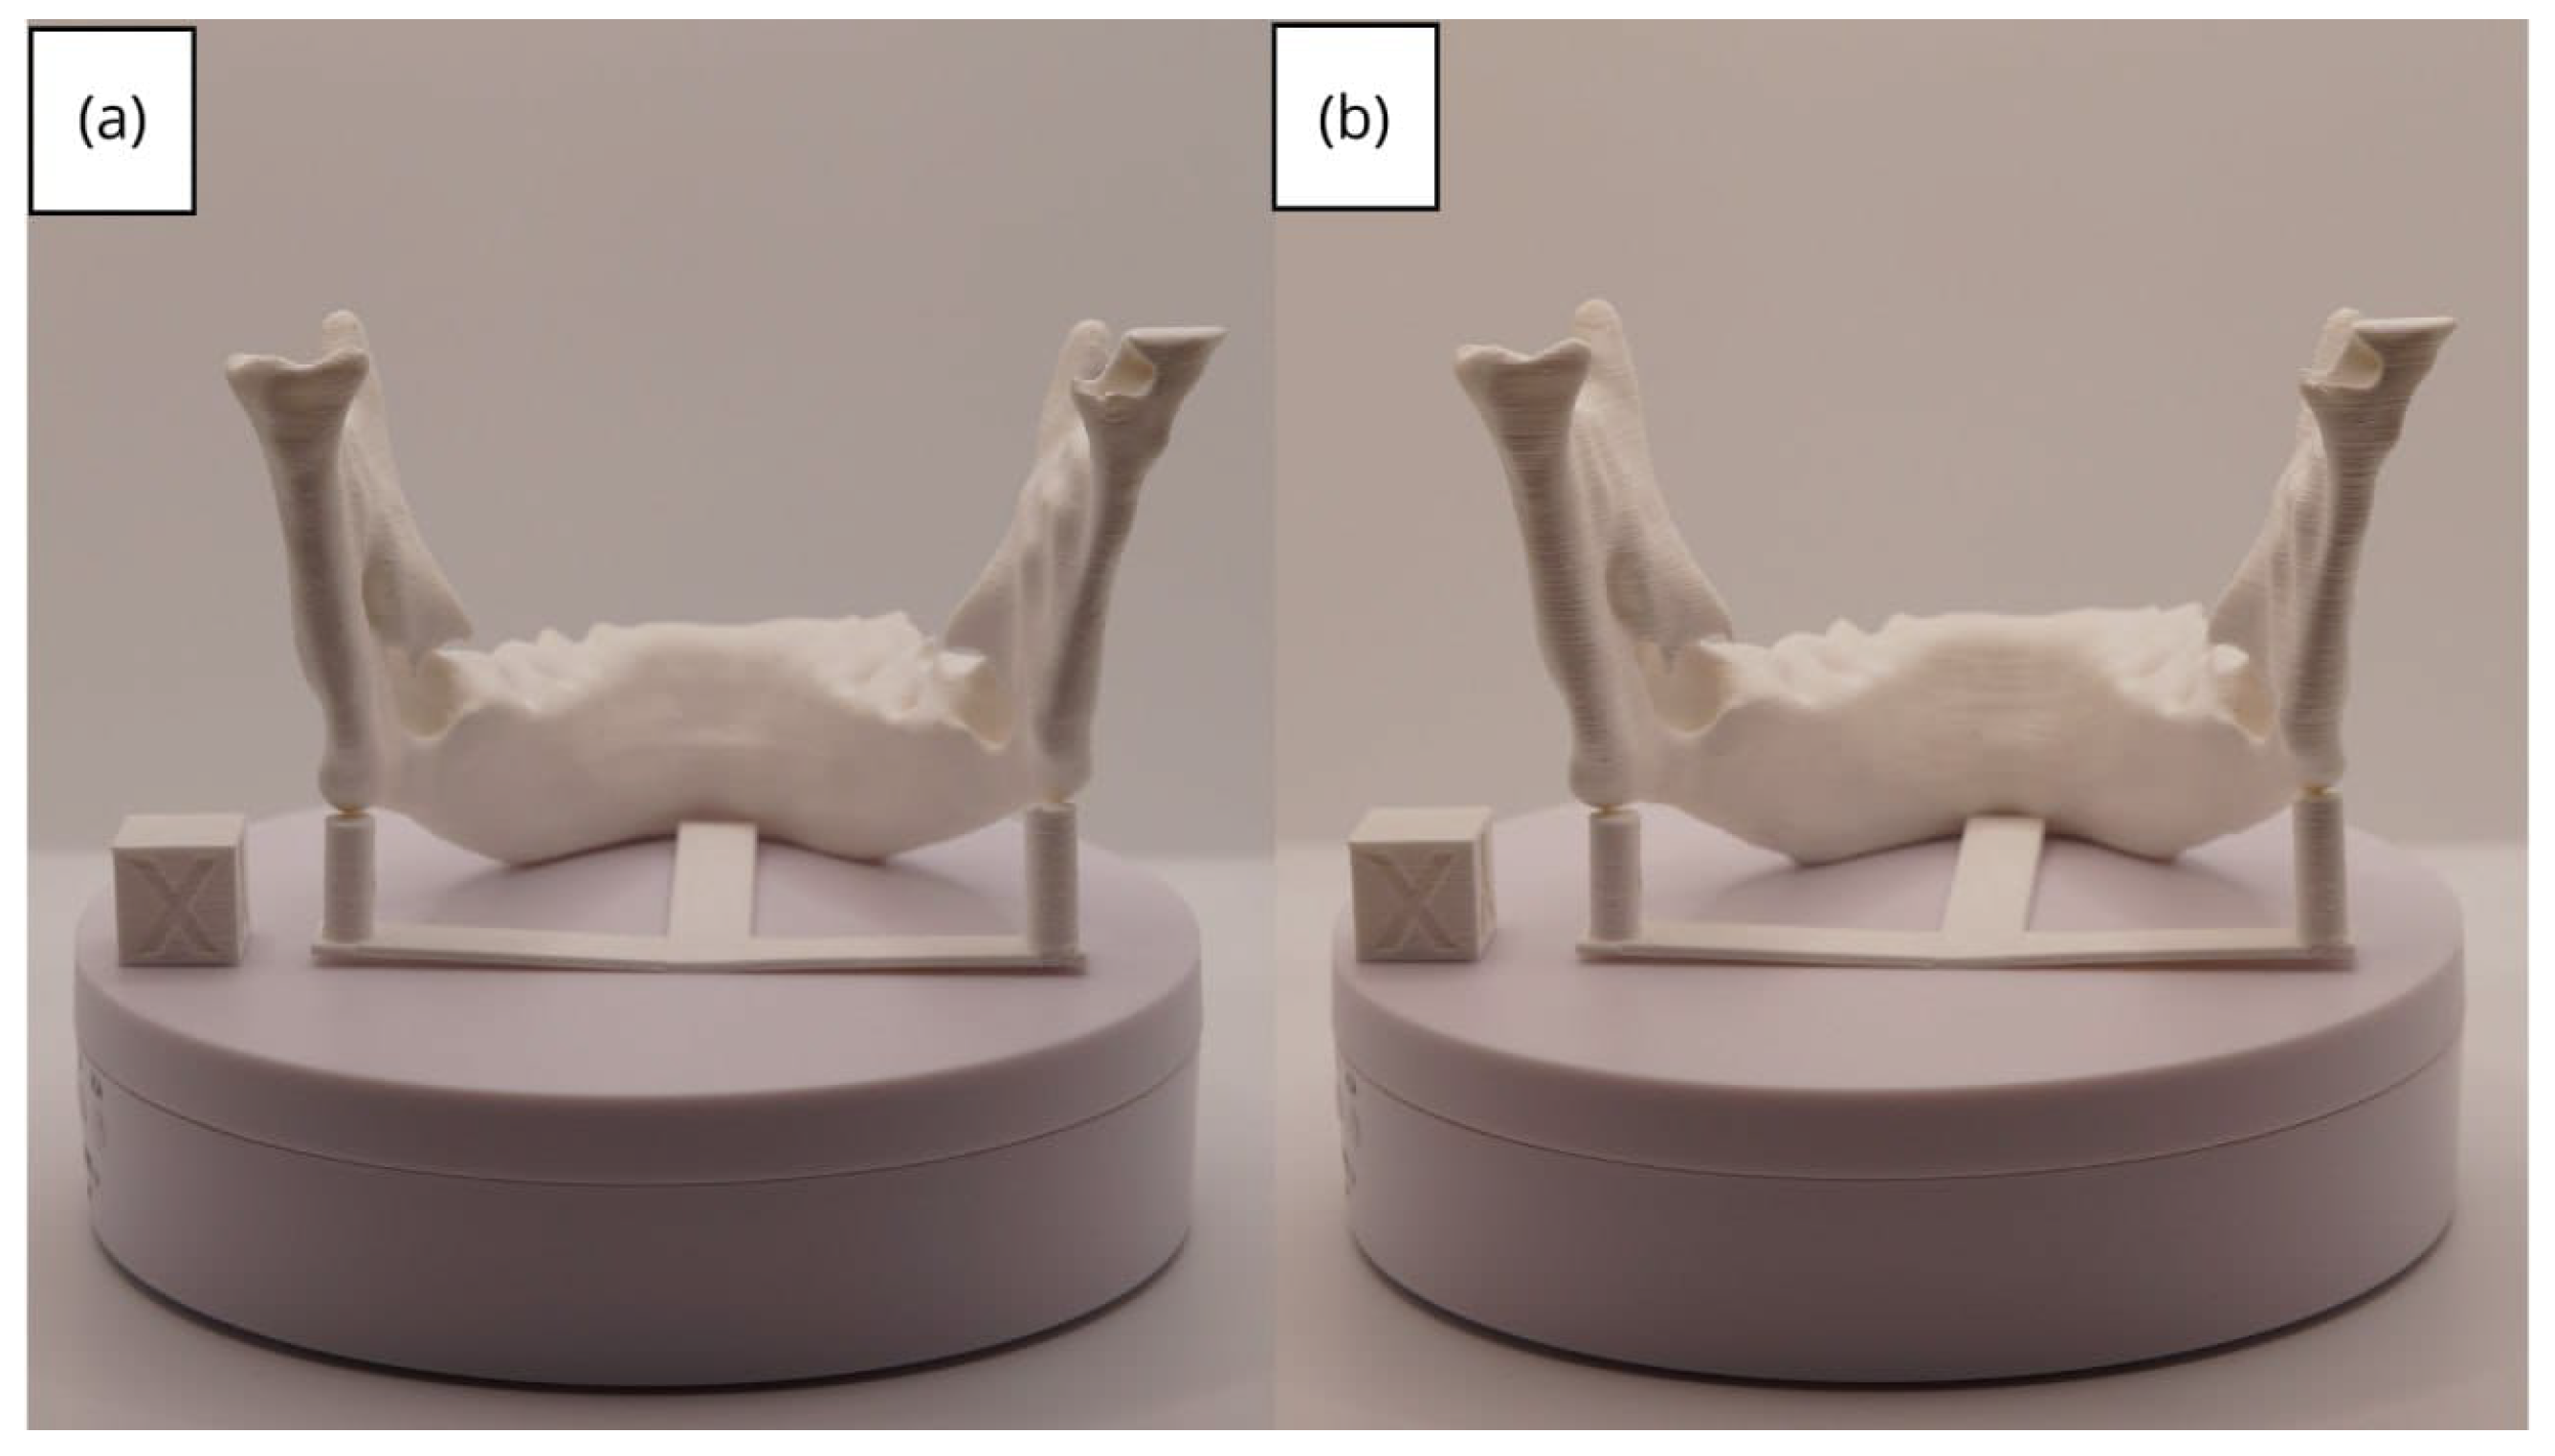

3.2. Human Lower Jaw

3.2.1. DICOM-to-STL Files

3.2.2. STL-to-GCODE Files

3.2.3. Final Printing

| Lower jaw models | m; m | Artillery Sidewinder X2 |

| m; m | Creality Ender 3 | |